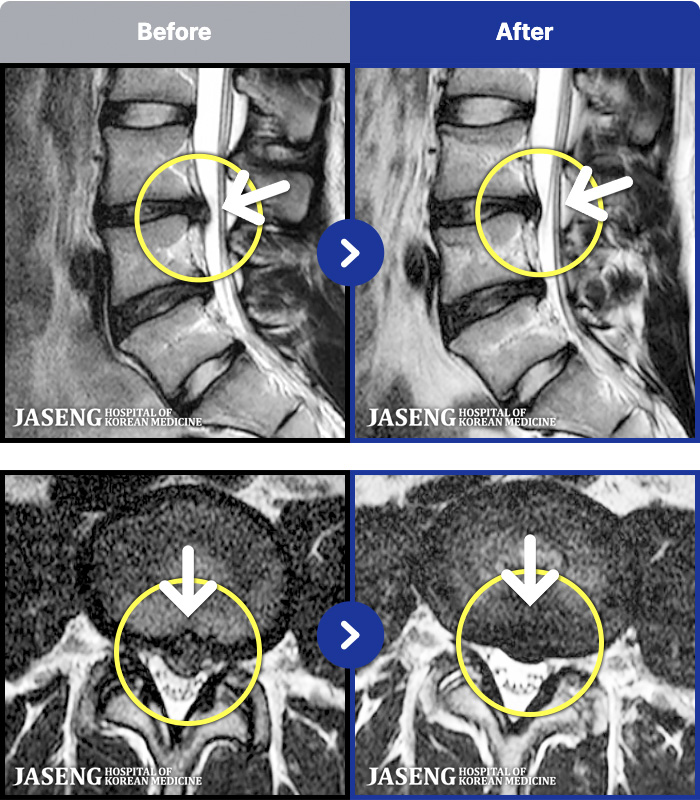

188 MRI ũ ʸ Ȯϼ.

ȯںп Ǹ ǿ ԿǾ, ο ġ ۿ Ƿ ġḦ Ͻñ ٶϴ.